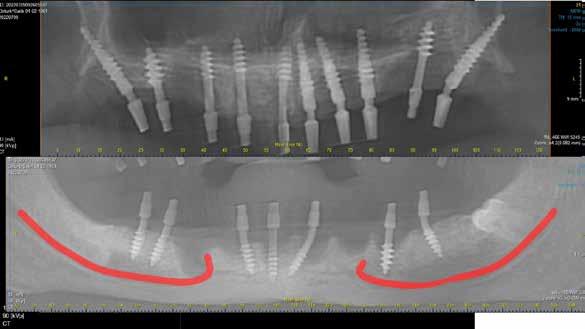

Saját gyermekeimnek már kb. 10 éves korukban készítettem OPT-ket a bölcsességfogak helyzetének ellenőrzése céljából. Mindkettejüknek 60-70°-os szögben mezioanguláltak a fogaik, tehát biztos, hogy nem fognak normál pozícióban az erupciós síkig emelkedni, ezért az eltávolításuk indokolt. Ezzel addig várok, amíg egyrészt a lehető legkisebb prepa-

A CT metszetekben a 48-as gyökerei körbeölelik a canalis mandibularist, amelyet piros nyíllal jelöltünk a fotókon.

rációval tudom felszabadítani a koronát, másrészt, hogy a gyökerek 1-2 mm-nél ne kerüljenek közelebb a canalishoz. A fejlődési ütemüket követve, előreláthatólag kb. 15-16 éves korukra érik el a fogaik ezt az állapotot.

Szeretnék mutatni néhány ábrát az egyik bonyolult esetről, a közelmúltból. A CT-n látszik, hogy a három gyökér teljesen „körbenőtte” az ideget. Van olyan frontális metszeti kép, ahol csak a gyökerek vannak a nervus körül, ezen a szakaszon egyáltalán nincs meg a csontos fala a canalisnak. Szeparációs technikával, viszonylag könnyen, minimális traumával, szövődménymentesen sikerült eltávolítani a fog minden részét. A várakozásnak megfelelően, a beteg nem számolt be paraesthesiáról.